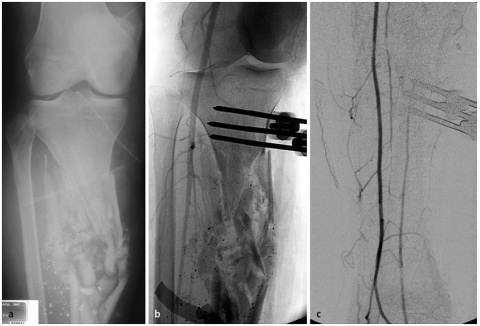

Beim Auftreffen des Projektils im Rahmen von Niedrigenergieverletzungen auf Knochengewebe entsteht meist eine typische, einfache Fraktur (Abbildung 2). Hochenergieverletzungen des Knochens münden in eine multifragmentäre Situation, bei der ein Großteil der Projektilenergie an den Knochen abgegeben wird. Insbesondere lange Röhrenknochen können, da sie wie eine starre, spröde flüssigkeitsgefüllte Röhre agieren, durch Projektile mit hoher Energie explosionsartig zerstört werden (Abbildung. 3).

Insbesondere bei Schussfrakturen verursacht durch Hochenergieprojektile ist neben ausgeprägten Weichteilverletzungen mit einer massiven Trümmerzone aus avitalen Knochenfragmenten zu rechnen. In diesen Fällen muss ein radikales Débridement sowohl der avitalen Weichteile, aber auch der avitalen Knochenfragmente erfolgen [1]. Aufgrund der hohen Kontaminationsrate durch in den Schusskanal gezogene Kleidungsreste und Fremdkörper mit entsprechend erhöhtem Infektionsrisiko [21, 43], ist die primäre Stabilisierung durch einen Fixateur externe das Mittel der Wahl [1]. Dies gilt insbesondere dann, wenn nicht eindeutig ist, ob um eine Niedrig- oder Hochenergieverletzung vorliegt. Dieses Vorgehen wird durch die Publikation von Long et al. [44] unterstützt. In dieser Arbeit bezüglich der Schussverletzungen am Femur wurde anhand von klinischen und radiologischen Befunden eine Einteilung in 3 Schweregrade vorgenommen. Während Grad-1-Verletzungen Niedrigenergieverletzungen waren, die allesamt primär mit einem Marknagel versorgt wurden, wiesen Grad-2- und Grad-3-Verletzungen Zeichen einer Hochenergieverletzung auf. Diese Patienten entwickelten im Verlauf in bis zu 50 % der Fälle eine tiefe Wundinfektion, was eindeutig gegen eine primäre osteosynthetische Ausversorgung spricht. Zudem waren bei Verletzungen der Grade 2 und 3 auch wiederholte Débridements notwendig.

der Schussfraktur des rechten Femurs zudem das noch oberhalb des Kniegelenks befindliche Projektil.

c: Klinisch bestehen ein Ein- und Ausschuss am linken Oberschenkel (rechter Bildrand) mit isolierter und unkomplizierter Weichteilverletzung sowie ein isolierter Einschuss am rechten Oberschenkel medial ohne dazugehörigen Ausschuss. Es wurde nur ein Schuss abgegeben.